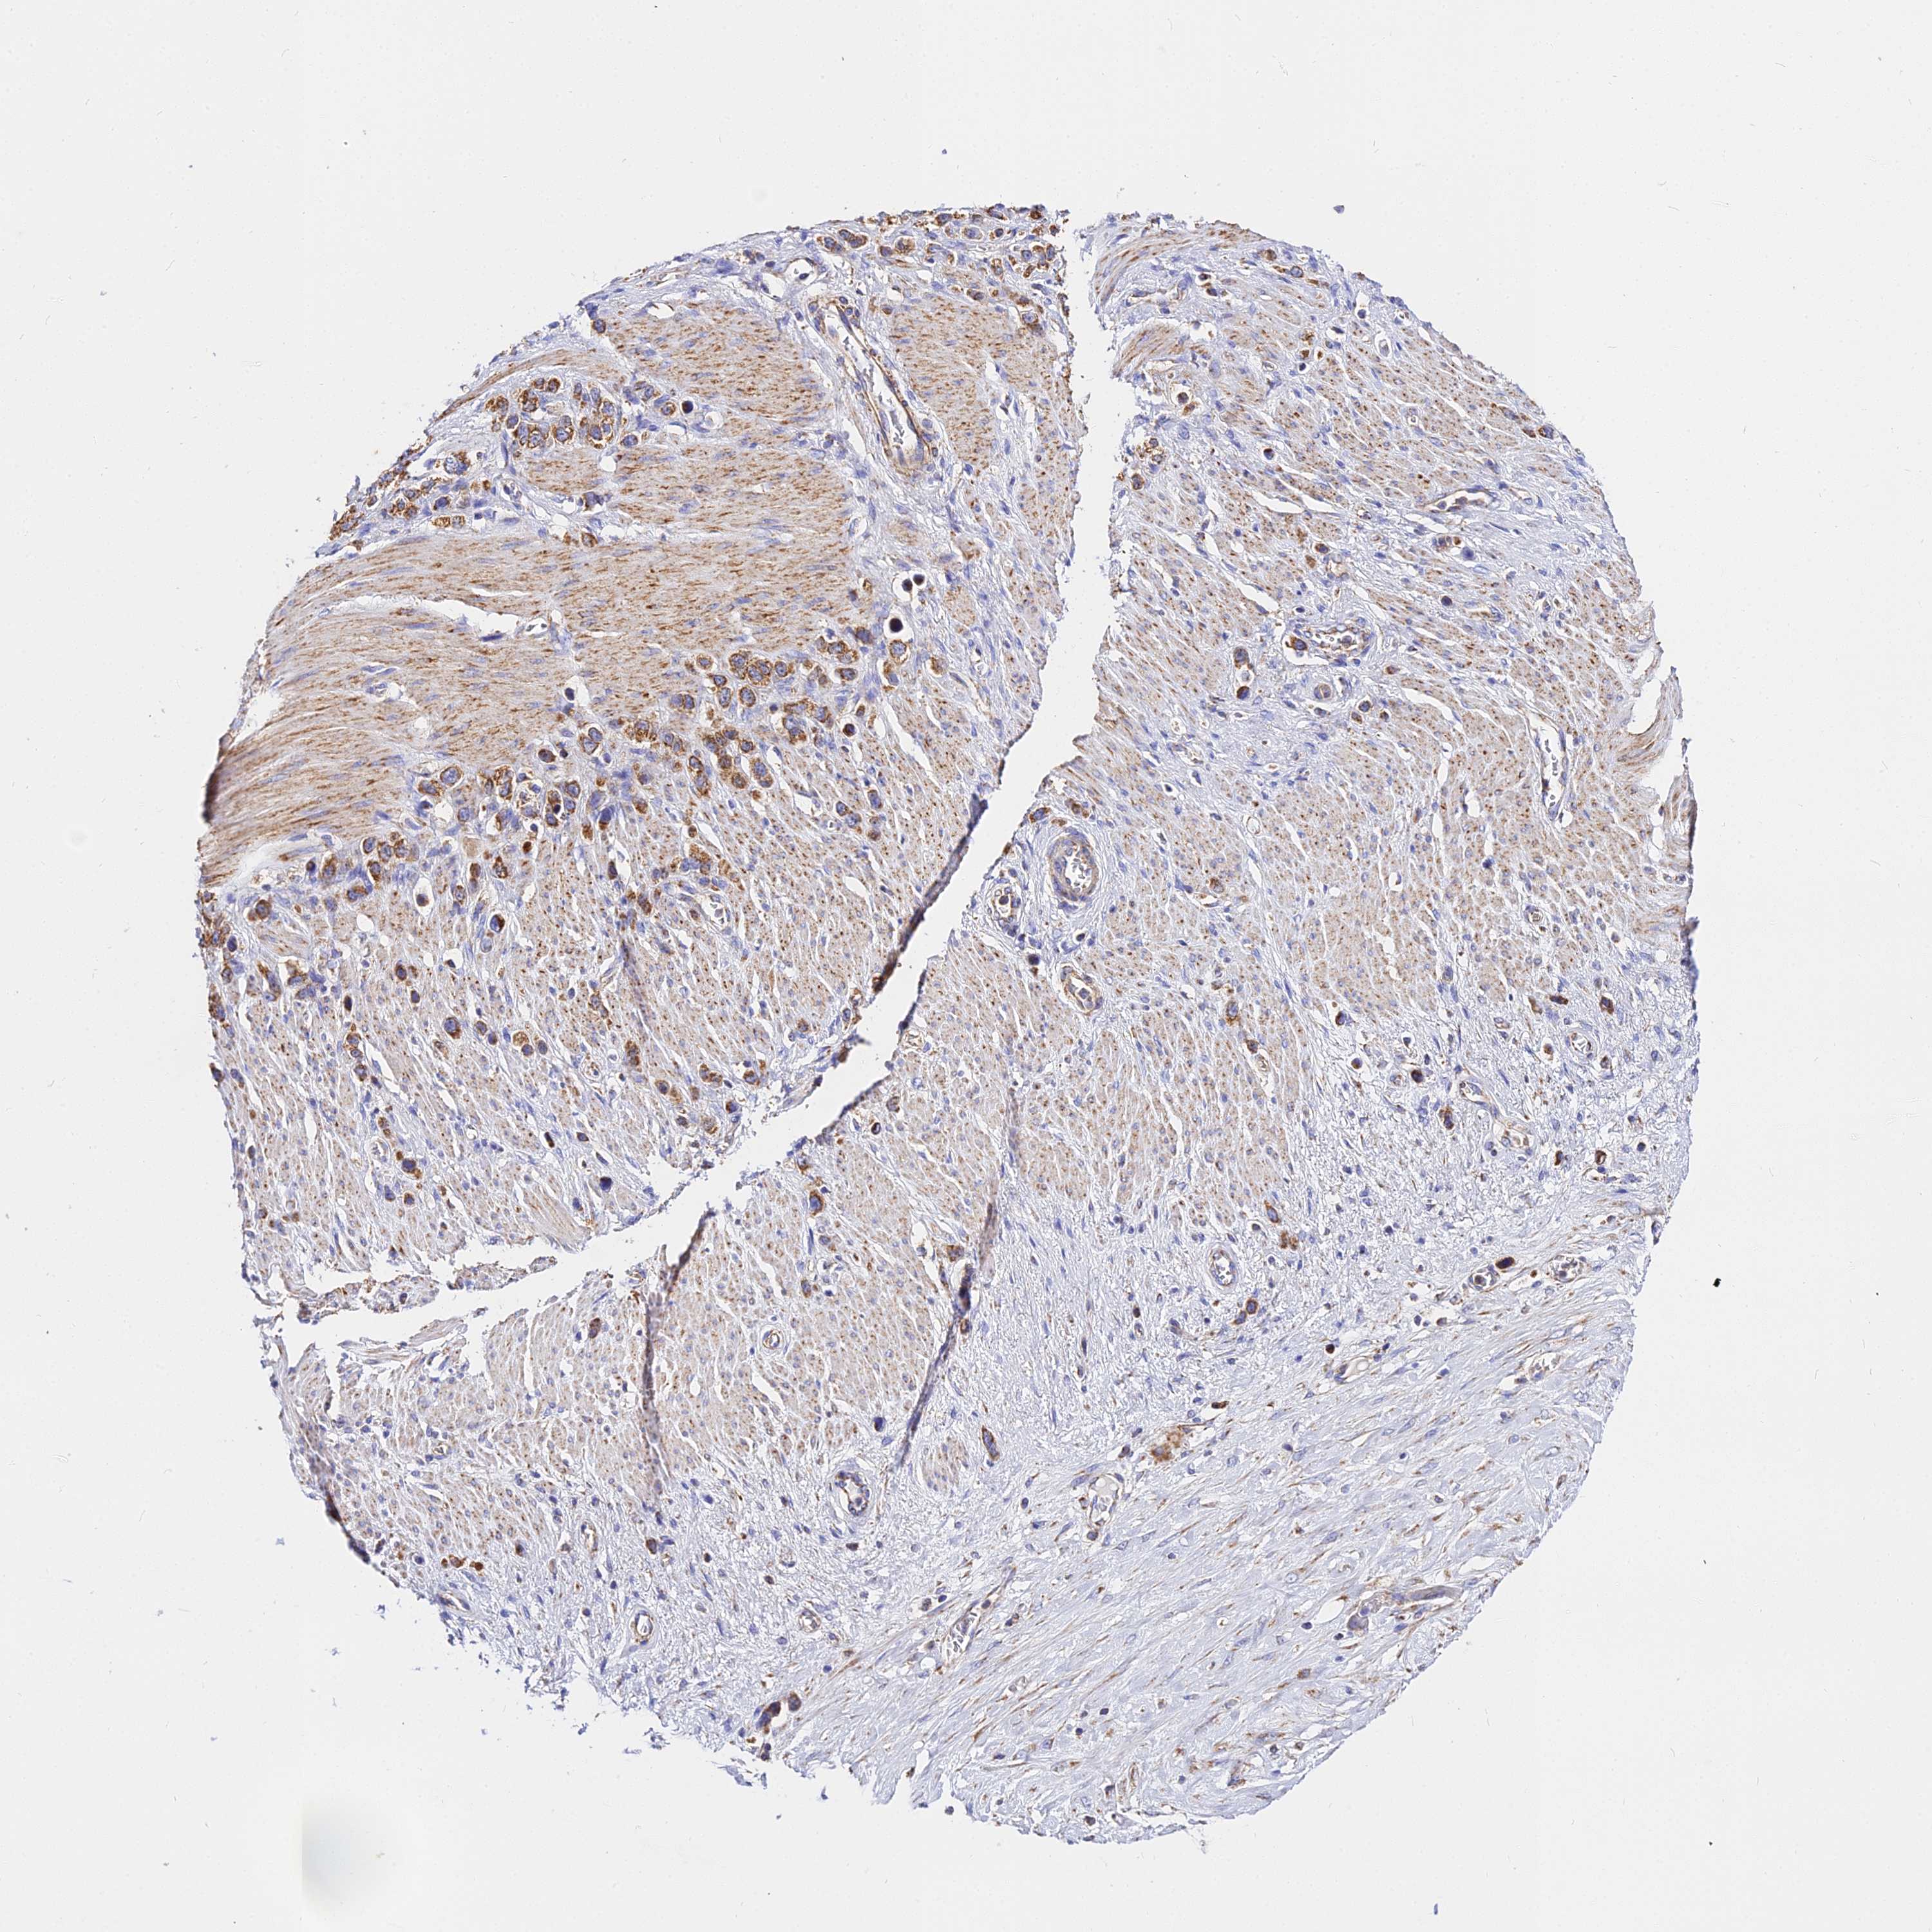

STOMACH CANCER - Protein expressioni

A mouse-over function shows sample information and annotation data. Click on an image to view it in a full screen mode. Samples can be filtered based on level of antibody staining by selecting one or several of the following categories: high, medium, low and not detected. The assay and annotation is described here.

Note that samples used for immunohistochemistry by the Human Protein Atlas do not correspond to samples in the TCGA dataset.

Antibody stainingi

Antibody staining in the annotated cell types in the current human tissue is reported as not detected, low, medium, or high, based on conventional immunohistochemistry profiling in selected tissues. This score is based on the combination of the staining intensity and fraction of stained cells.

Each image is clickable and will lead to virtual microscopy that enables deeper exploration of all samples and also displays staining intensity scores, fraction scores and subcellular localization as well as patient and tissue information for each sample.

Antibody HPA042776

Staining

High

Medium

Low

Not detected

Intensity

Strong

Moderate

Weak

Negative

Quantity

>75%

75%-25%

<25%

None

Location

Nuclear

Cytoplasmic/membranous

Cytoplasmic/membranous,nuclear

Adenocarcinoma, NOS

Adenocarcinoma, High grade